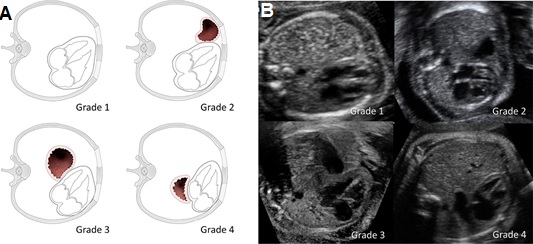

5.3 Vị trí dạ dày

Đánh giá vị trí dạ dày gần đây đã được đưa vào như một phương pháp gián tiếp để đánh giá mức độ nghiêm trọng của bệnh trong CDH bên trái. Nếu dạ dày còn ở trong bụng thì có tiên lượng tốt hơn dạ dày nằm trong lồng ngực. Gần đây Cordier và cộng sự đã khẳng định vị trí của dạ dày giúp tiên đoán tỷ lệ sống còn sau sinh [7]. Một số nghiên cứu khác cũng khẳng định vị trí của dạ dày có liên quan rõ với tỷ lệ tử vong sơ sinh, sự cần thiết của ECMO và tình trạng suy hô hấp của trẻ ngay sau sinh. Vị trí của dạ dày trong lồng ngực có tương quan với tỷ lệ tử vong và bệnh tật sau sinh và độc lập với o/e LHR [11].

* Điểm thực hành

Vị trí của dạ dày được phân độ như sau:

- Độ 1 hoặc bụng: dạ dày ở vị trí bình thường do đó không được nhìn thấy trong lồng ngực

- Độ 2 hoặc phía trước trái trong lồng ngực: dạ dày được nhìn thấy ở phía trước đỉnh tim, tiếp xúc với thành trước ngực

- Độ 3 hoặc từ giữa đến sau ngực trái: dạ dày không tiếp xúc với thành trước ngực trái; tuy nằm cạnh van nhĩ thất nhưng với phần lớn hơn của nó vẫn ở phía trước

- Độ 4 hoặc sau tim: hầu hết dạ dày nằm sau van nhĩ thất, bên cạnh tâm nhĩ trái của tim ở trong lồng ngực phải

Hình 8. Hình vẽ phác họa (A) và hình ảnh siêu âm (B) của thai nhi có CDH bên trái và vị trí dạ dày khác nhau. Độ 1: Dạ dày không thấy trong lồng ngực. Độ 2: Dạ dày tiếp xúc với thành ngực trước. Độ 3: Dạ dày cạnh van nhĩ thất nhưng vẫn chiếm ưu thế phía trước. Độ 4: Hầu hết dạ dày nằm sau van nhĩ thất.[7]